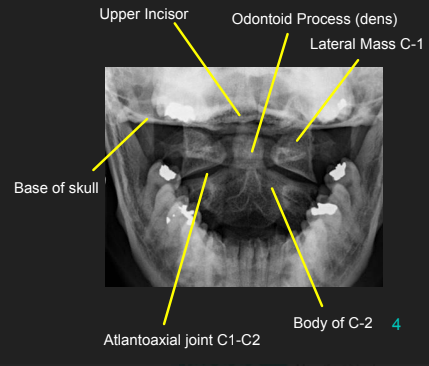

AP Open Mouth: Eval Criteria

Entire odontoid process, atlantoaxial joint, and lateral masses of C1 demoed

Upper incisors and base of skull are superimposed

Atlantoaxial joint is symmetrical